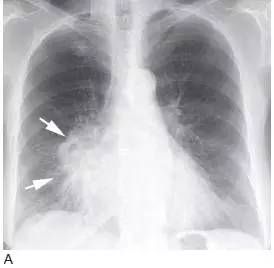

图1 表现为支气管管腔内和肺门肿块的鳞状细胞癌

A.CT 显示右下叶支气管内息肉状的肿块( 箭头),为典型的鳞状细胞癌;

B. 在稍低层面,支气管腔阻塞伴局部浸润,导致肺门肿块(M)